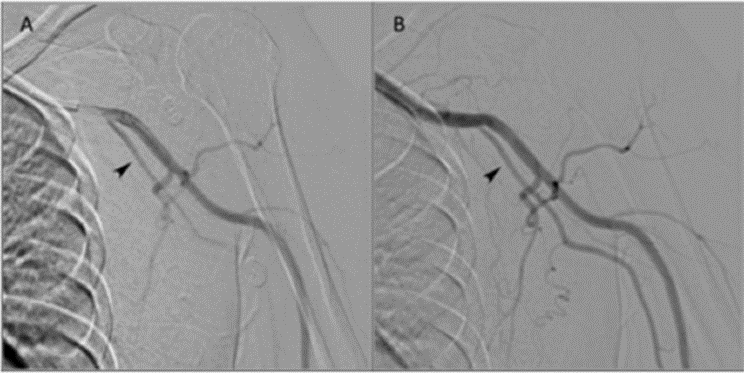

★ Case 2

肱尺动脉变异,吻合口远端动脉窃血导致HAIDI

男性,53岁,因高血压肾病,尿毒症,8个月前于建立左腕部RCAVF。手术后即感觉左手发凉及麻木,术后5个月开始出现左第2、3指静息痛,第2指指尖破溃不愈合

US及DSA提示肱尺动脉变异,吻合口远端动脉返流